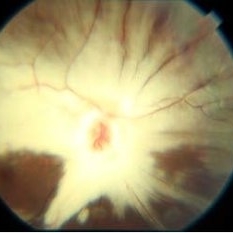

Myelinated Nerve Fibre (MNF)

Sep 12 2023 by Ben Serar

Fundus photograph of RE showing Myelinated Nerve Fibre along superior disc margin

Condition/keywords: MNF, myelinated nerve fiber